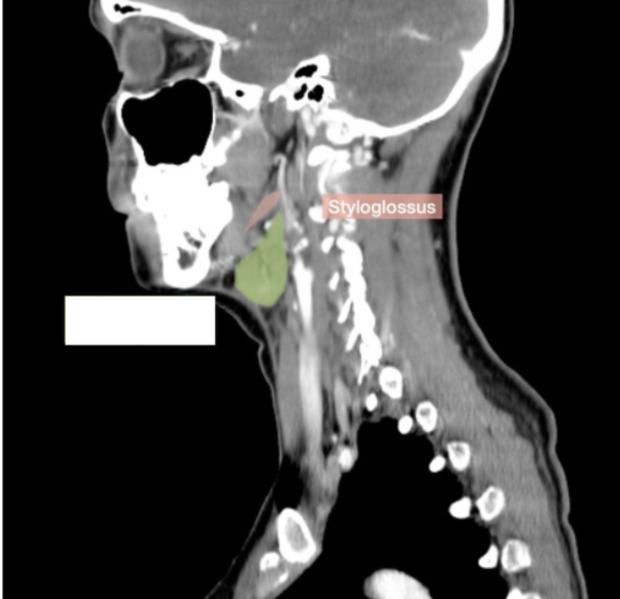

Please label